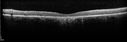

65 year old woman with gradually declining central vision. VA 20/200 in both eyes in the later photos (left eye was better in earlier photos). FAF shows pisciform tri-radiate lesions that are hyper FAF typical of stargardt's fundus flavimaculatus